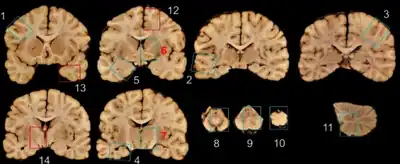

| A normal brain (left) and one with CTE (right) | |